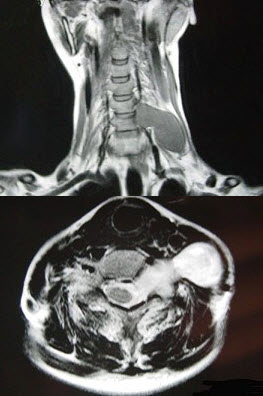

52岁女性患者,左颈部无痛性包块渐进性增大,MRI检查如图,应考虑为()。

A、左侧颈部神经鞘瘤

B、左侧颈部神经纤维瘤

C、左侧颈部动脉瘤

D、左侧颈部转移癌

E、左侧颈部脂肪瘤

A